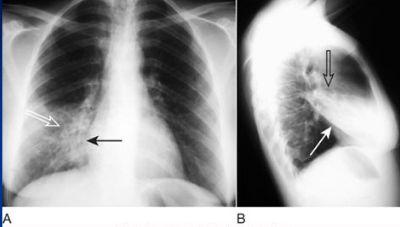

相关图片